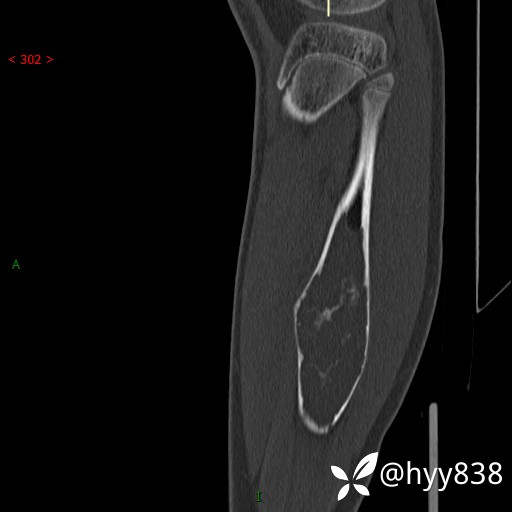

SAG